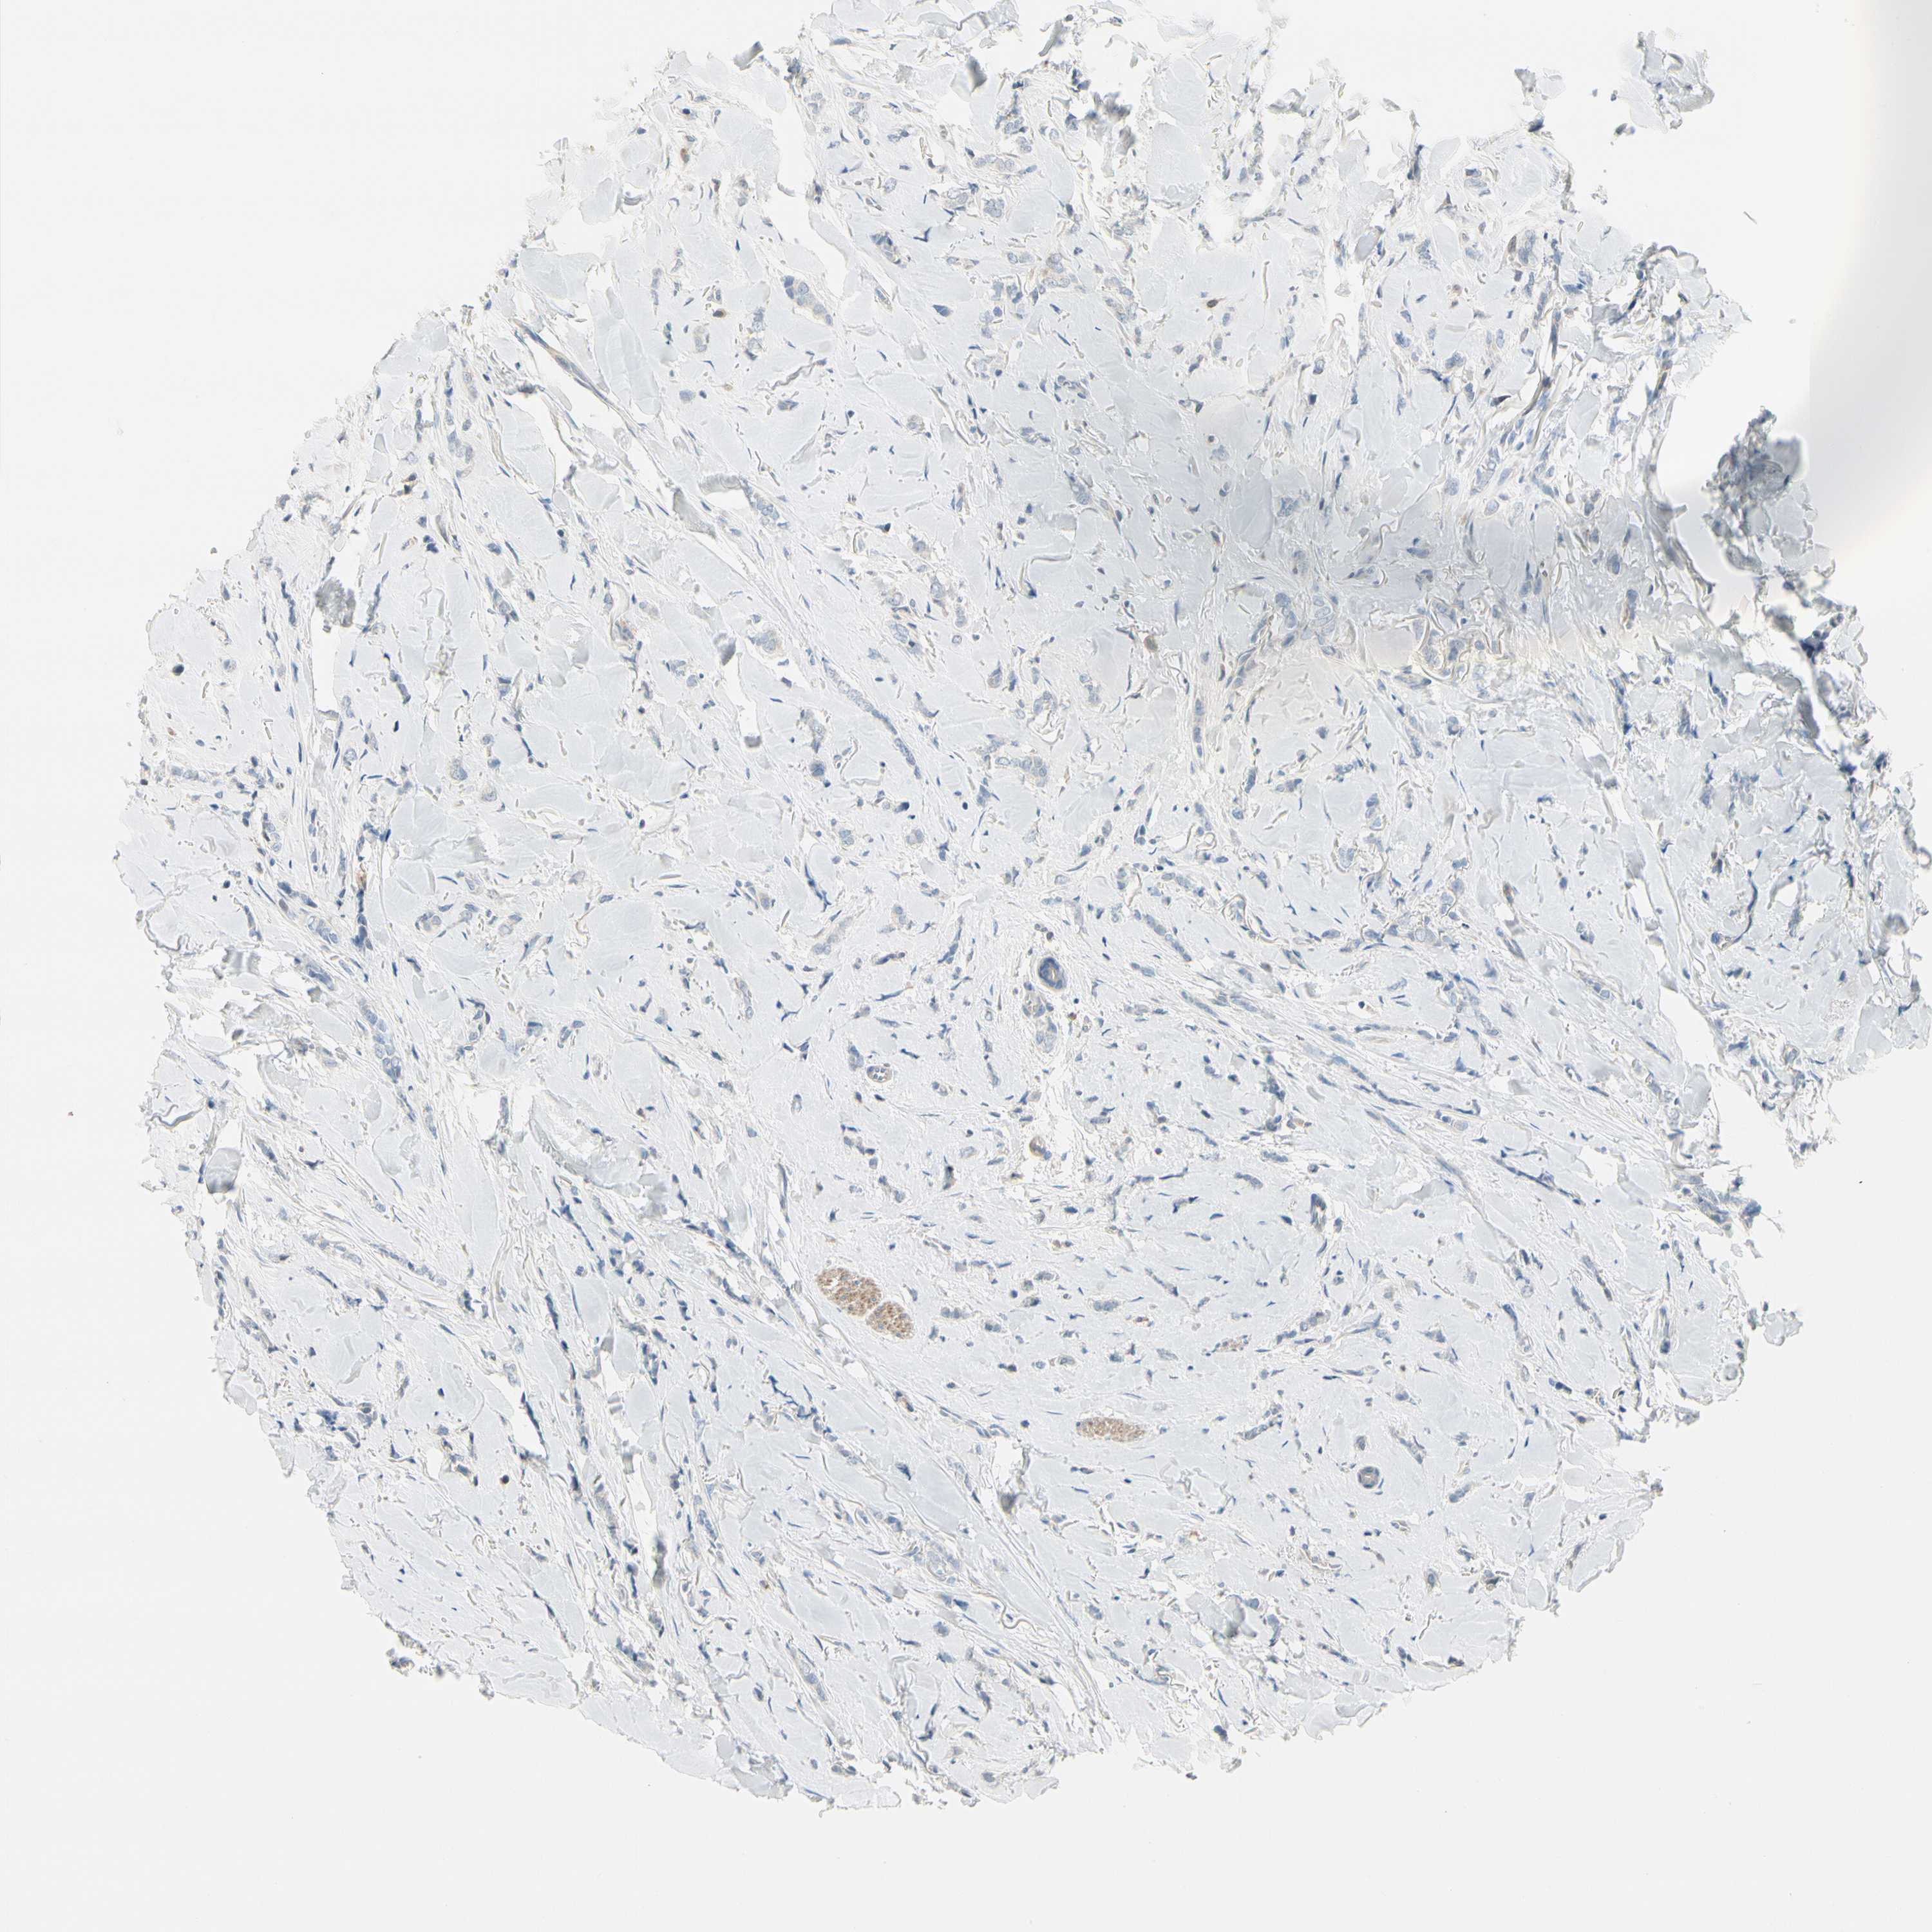

BRCA TCGA BRCA VALIDATION PROTEIN EXPRESSION

ANTIBODIES

AND

VALIDATION